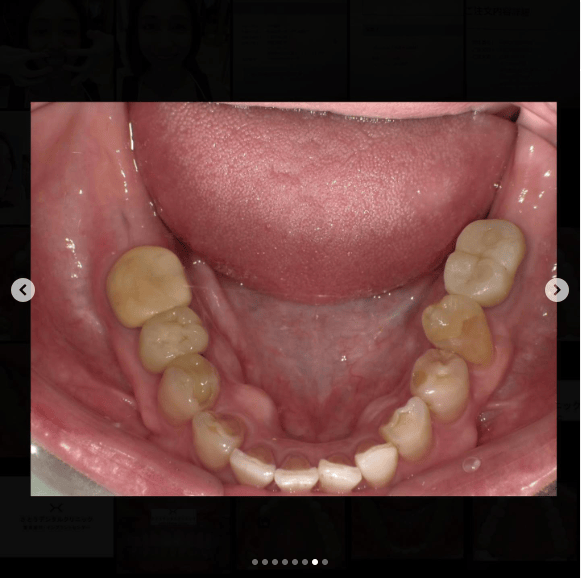

「ずっと放置してしまっていた。今回はちゃんとしっかり治したい」ということで、強い意志をもって来院してくださった患者様の症例です。

インプラント治療、セラミック治療、歯周病治療により、審美性と機能、咬みあわせの再建を行いました。

患者様は咬みあわせの確立により、食事もしやすく、普段の顎関節の状況も良くなり、機能の回復にも満足してくださり、また審美性も喜んでくださいました。

放置期間が長くだいぶ骨が溶けてしまっていたので、前歯部のインプラントは骨の再生療法などが必要だったりしましたが、患者様が治療への前向きな姿勢をだしてくださっていましたので期間も最短で終わりました。

一度放置してしまうと、億劫になってしまってなかなか行動に移すのは難しいと思いますが、少しでも早く治してあげた方が毎日の食事も楽になりますし、お顔の見栄えもお顔の骨格の歪みも改善します。